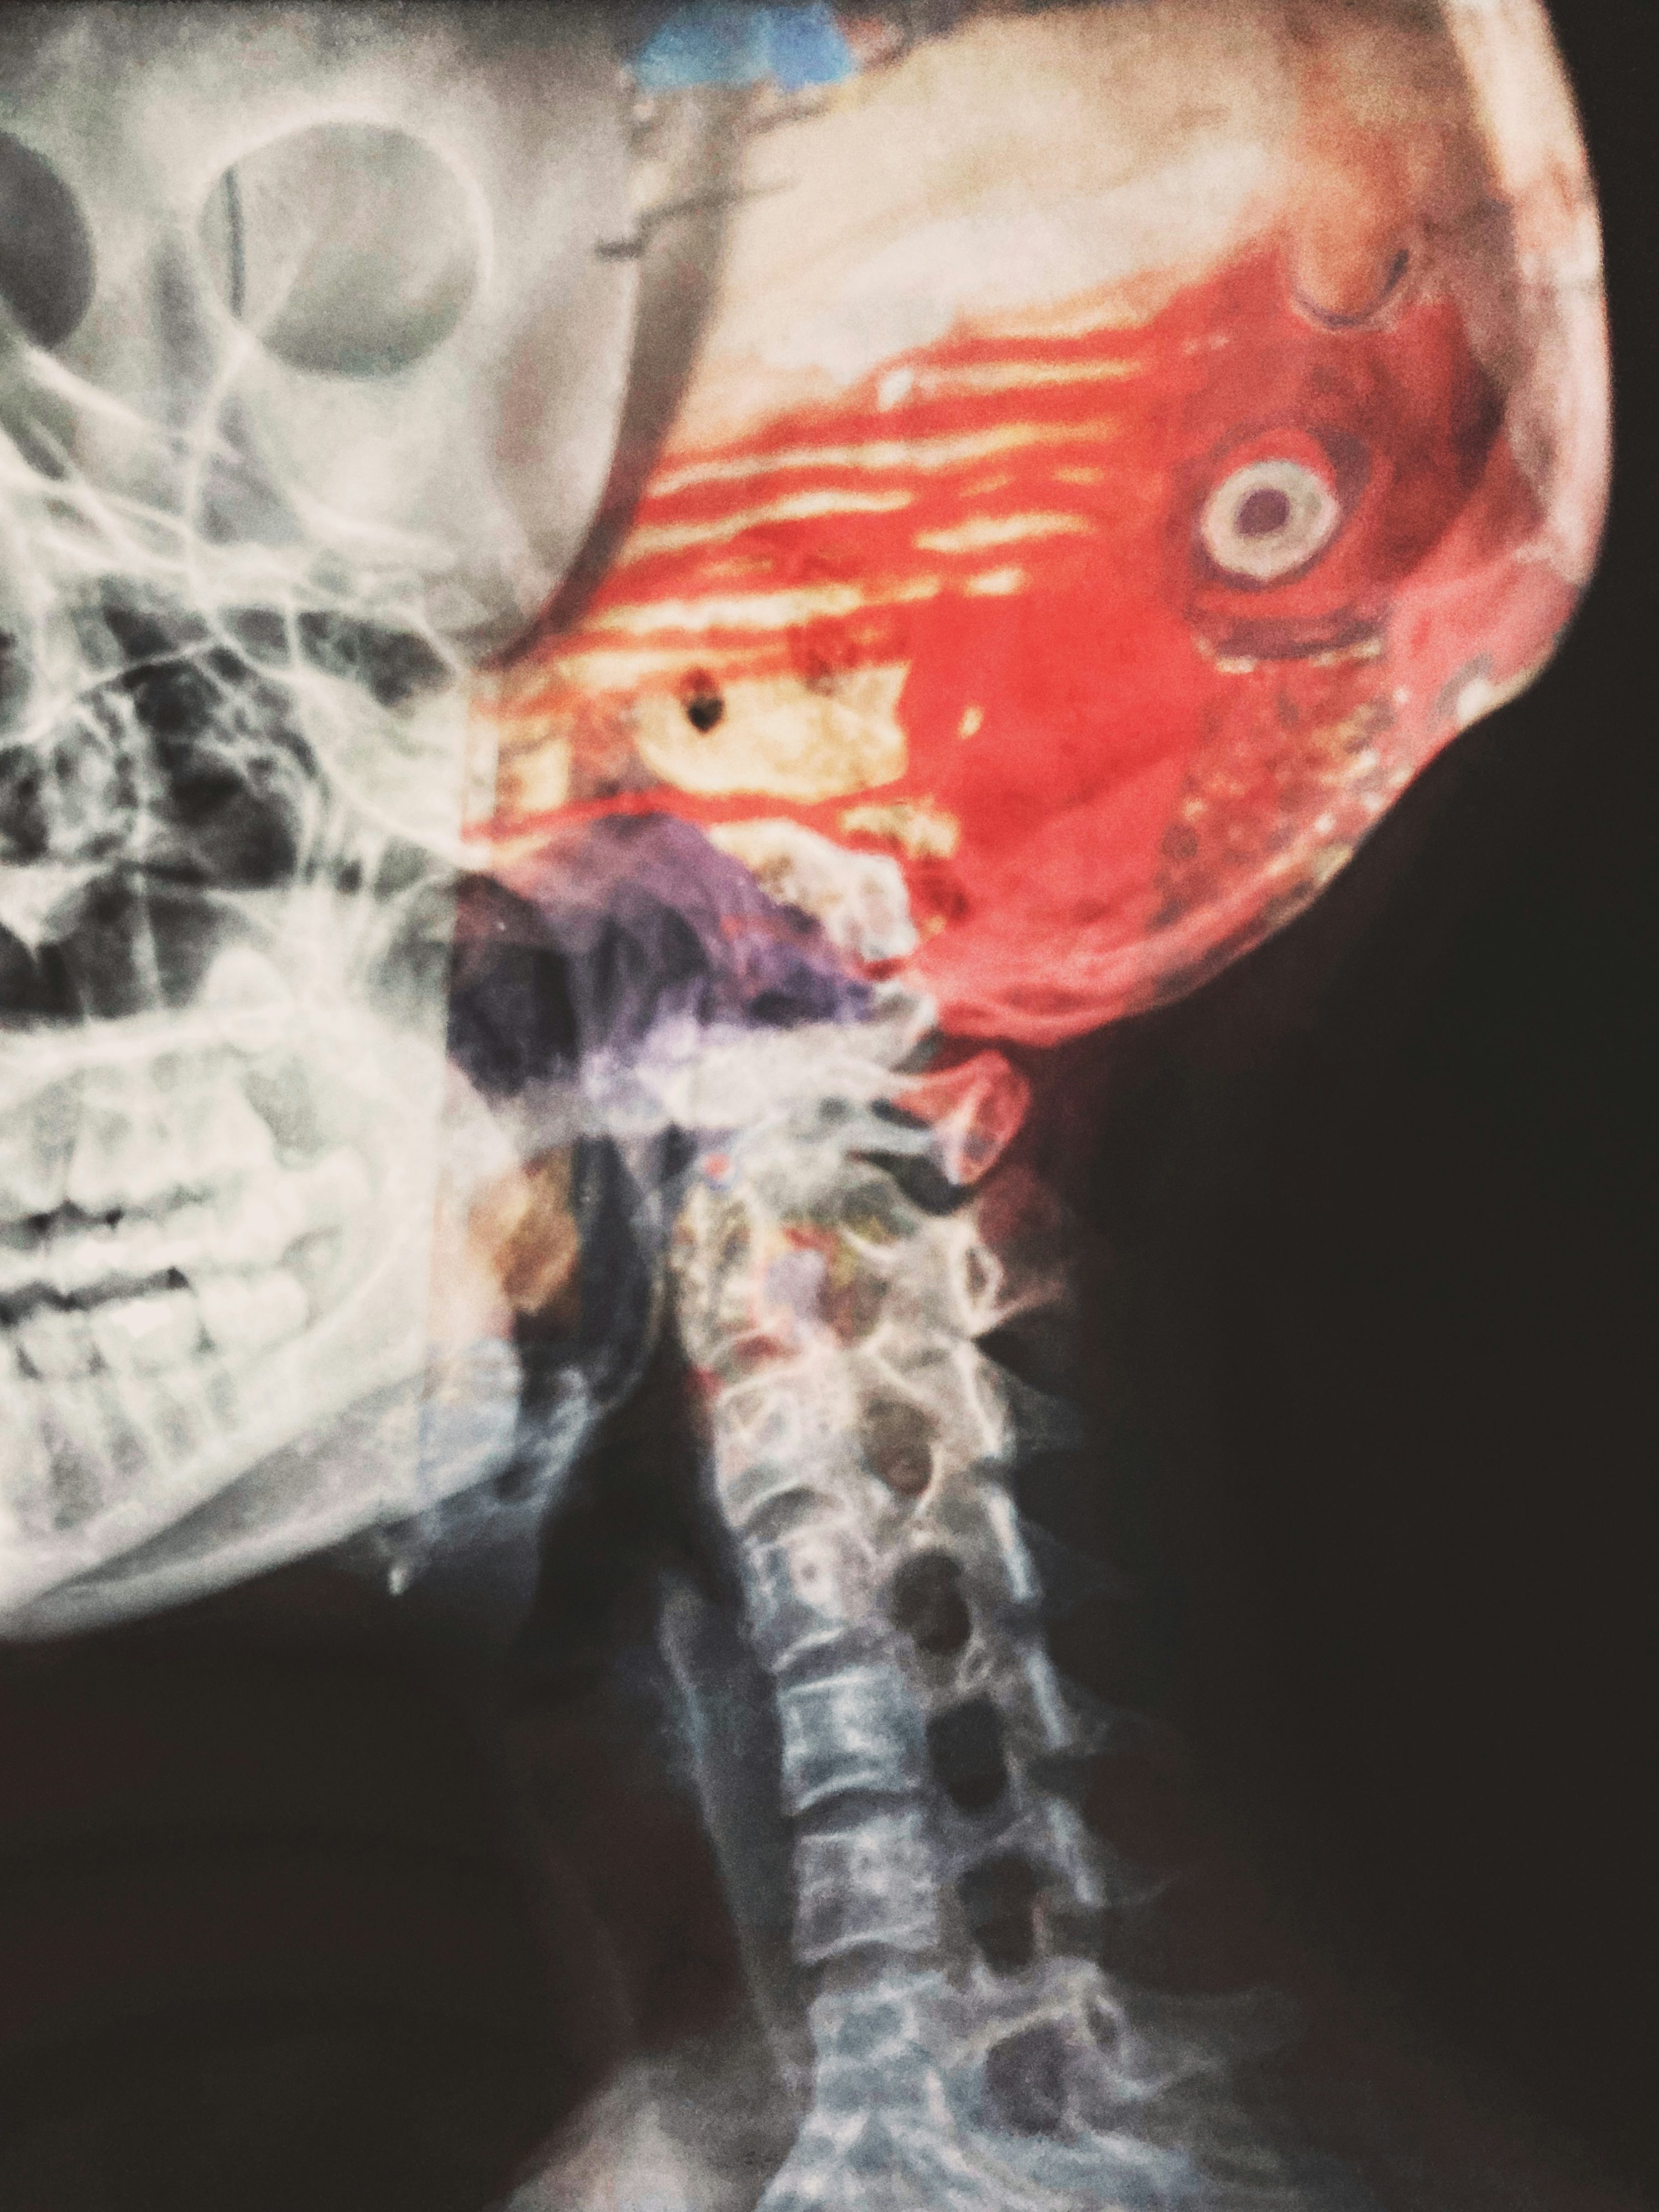

뇌경색 치료방법으로 최근 각광받는 것이 기계적 혈전제거술입니다. 대혈관 폐색으로 인한 뇌경색에서 증상 발생 후 6시간 이내, 경우에 따라 24시간 이내까지 시행할 수 있는 치료법입니다. 사타구니 혈관을 통해 카테터를 삽입하여 뇌혈관까지 도달한 후, 스텐트나 흡입 장치로 혈전을 직접 제거하는 시술입니다. 혈전용해술보다 시간 창이 길어 더 많은 환자가 혜택을 받을 수 있습니다.

기계적 혈전제거술은 혈전용해술에 반응하지 않거나 금기 사항이 있는 환자에게도 시행할 수 있습니다. 특히 내경동맥이나 중대뇌동맥 같은 큰 혈관이 막힌 경우 효과가 매우 뛰어나며, 성공적으로 혈관이 재개통되면 극적인 회복을 보이기도 합니다. 연구에 따르면 기계적 혈전제거술을 받은 환자의 약 46%가 기능적으로 독립적인 생활이 가능한 수준으로 회복됩니다.

시술은 신경중재시술 전문의가 수행하며, 보통 1-2시간 정도 소요됩니다. 국소 마취 또는 진정 상태에서 진행되며, 실시간 영상 장비로 혈관을 확인하면서 혈전을 제거합니다. 혈전 제거 후 즉시 뇌혈류가 회복되면 환자의 증상이 극적으로 호전되는 경우도 있습니다. 혈전용해술과 기계적 혈전제거술을 병행하면 더욱 좋은 결과를 얻을 수 있습니다.

기계적 혈전제거술도 합병증이 있을 수 있습니다. 시술 중 혈관 손상이나 혈관 천공으로 인한 출혈, 색전이 떨어져 나가 다른 혈관을 막는 경우 등이 발생할 수 있습니다. 하지만 전문의의 숙련도가 높아지면서 합병증 발생률은 크게 감소하고 있습니다. 뇌경색 치료방법 중 골든타임을 놓친 환자에게 마지막 희망이 될 수 있는 치료법이므로, 증상 발생 후 가능한 한 빨리 병원에 도착하는 것이 중요합니다.